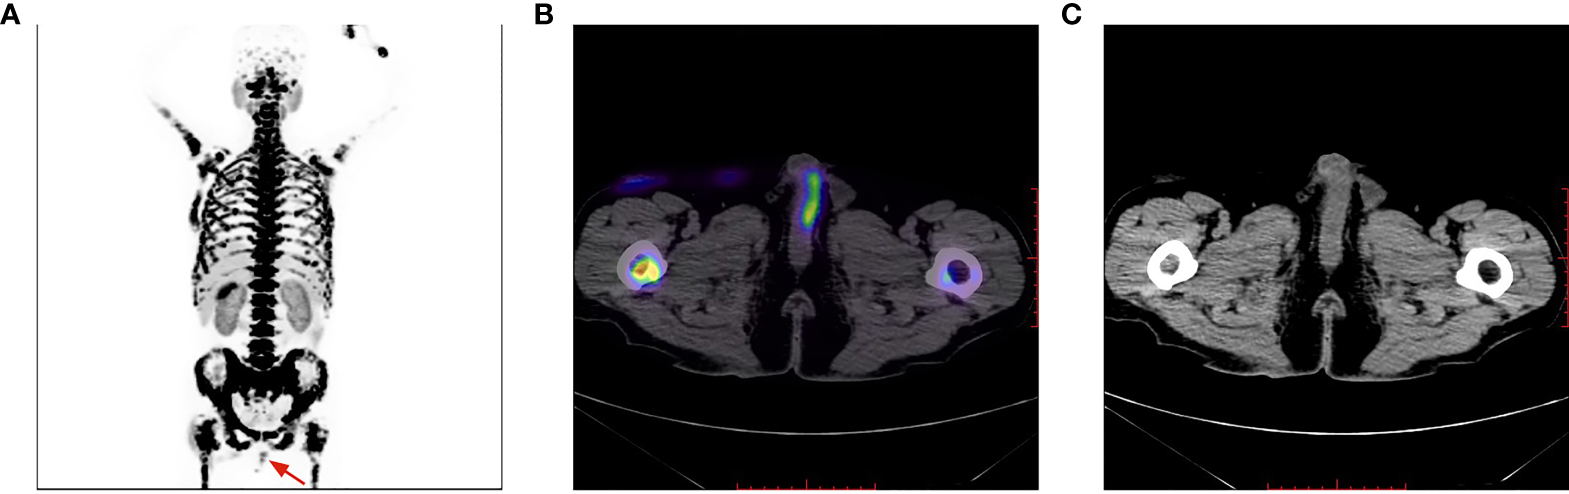

Figure 6

Penile lesion was enlarged with a higher SUVmax of 7.4 (B); meanwhile, systemic bone metastasis was certifified (A). No morphological abnormalities of the penis detected on CT imaging (C).